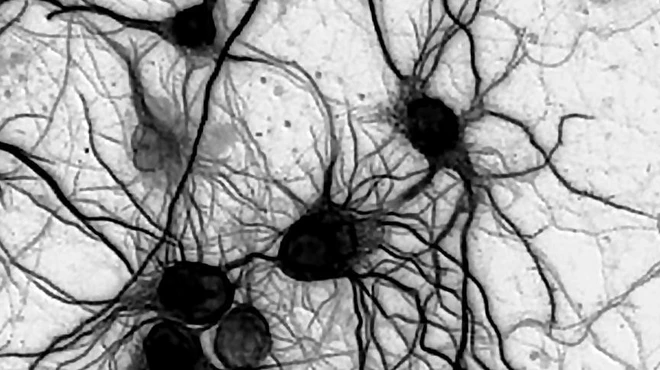

Eye disease tracked to a glitch in starburst cells

• Story